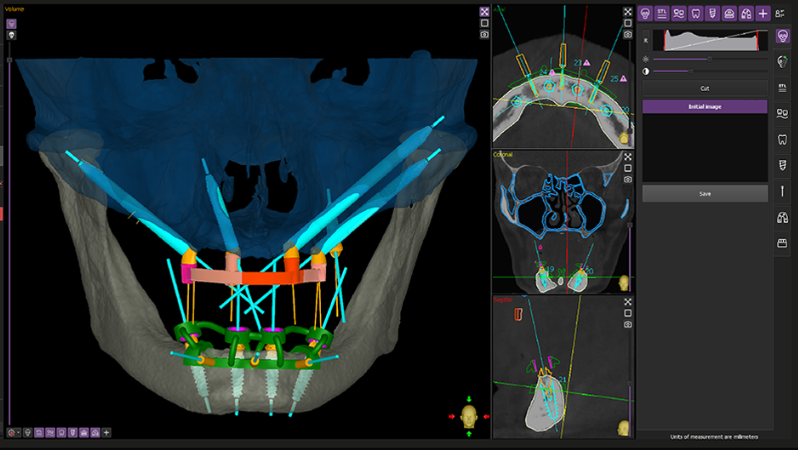

Bước 1: Khám & chẩn đoán

- Chụp CT Cone Beam 3D

- Đánh giá xương hàm và sức khỏe tổng quát

Bước 2: Lập kế hoạch điều trị

- Xác định số lượng và vị trí trụ Implant

- Lựa chọn loại hàm và vật liệu phù hợp

- Trụ được đặt chính xác theo thiết kế, có thể đặt nghiêng để tối ưu xương

- Thăm khám kỹ lưỡng bằng công nghệ 3D hiện đại